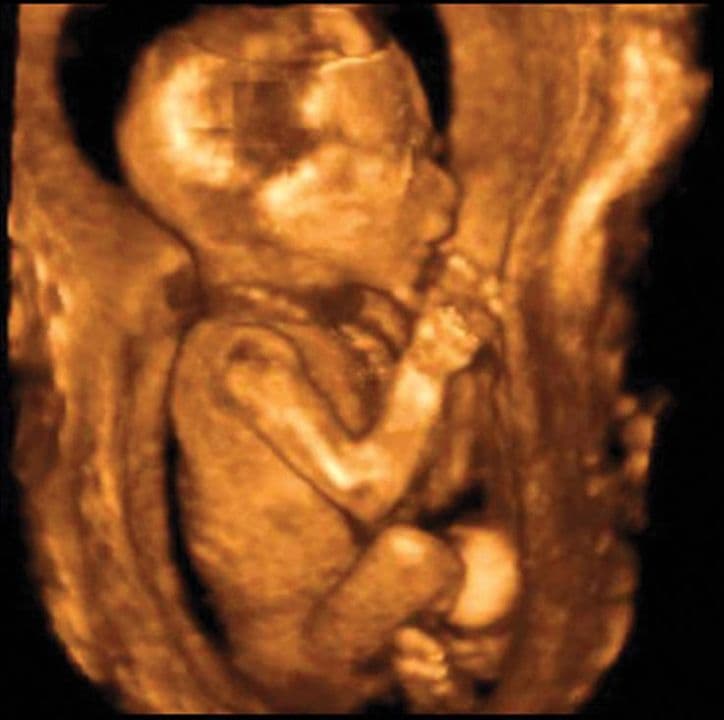

This is a side view ultrasound scan with the baby’s head in the top left. Your baby appears completely human with all fingers and toes fully developed. The skin is now covered with lanugo, fine protective hair.